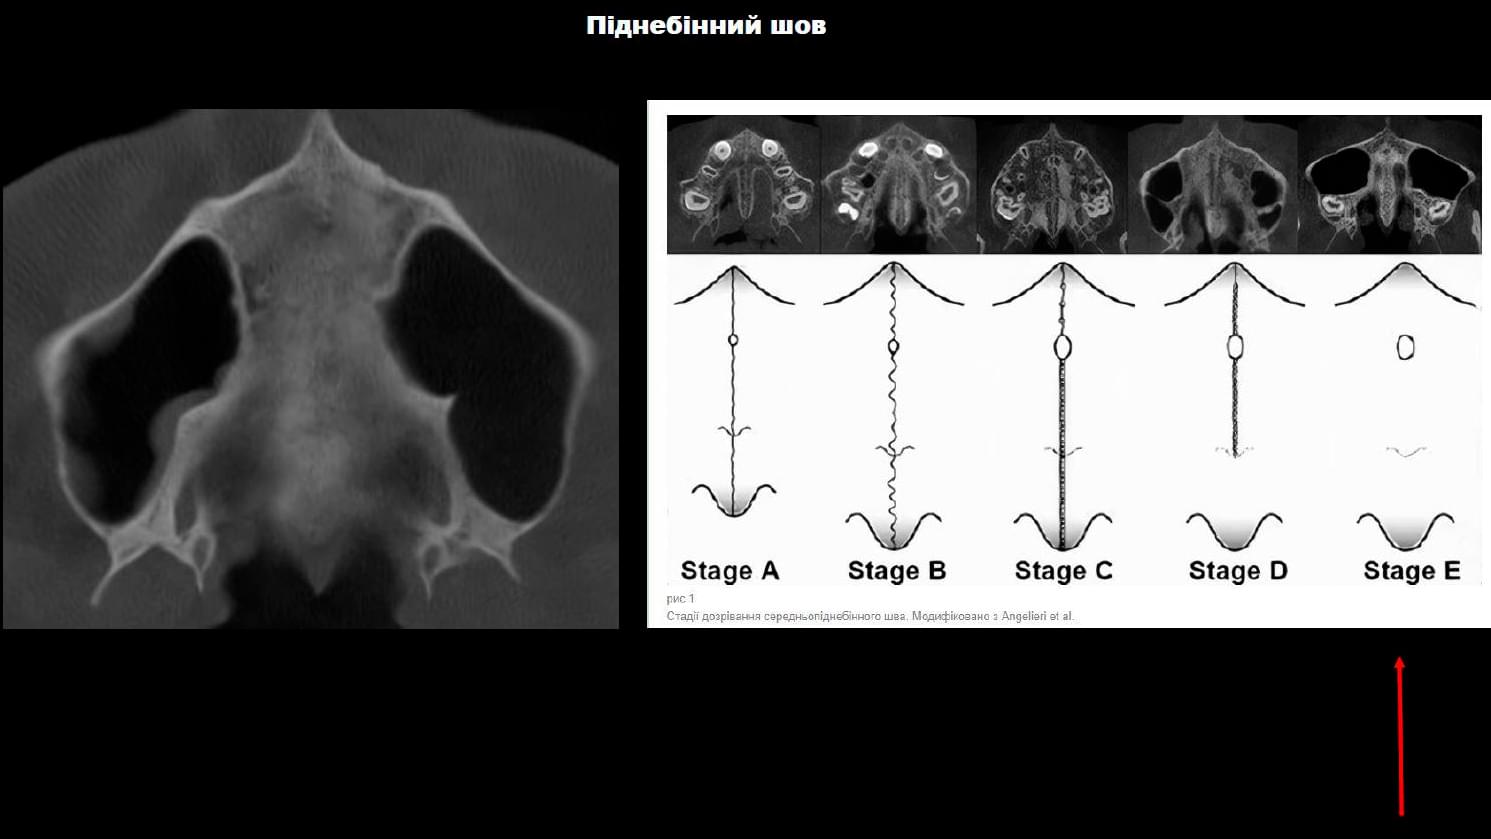

🔹 Навколоносові синуси: Зрізи в різних проекціях (аксіальна, коронарна, сагітальна) для

виявлення запалень, кіст або потовщення слизової.